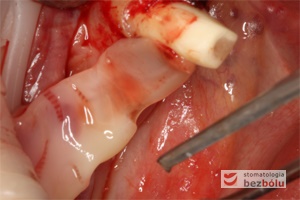

To autogenna matryca pochodząca z płytek krwi pacjenta, zawierająca czynniki przyspieszające angiogenezę poprzez trwałe uwalnianie płytkowego czynnika wzrostu (PDGF) będącego białkiem transformującym czynnik wzrostu. Stymulacja wzrostu tkanek dzięki białkowym czynnikom wzrostu znacząco przyspiesza gojenie tkanek tuż po zabiegach chirurgicznych. Powolne uwalnianie czynników wzrostu z PRF ma miejsce przez okres dłuższy niż 8 dni po zdeponowaniu A-PRF w miejscu pozabiegowym. Ten własny wartościowy materiał autogenny uzyskiwany jest z żylnej krwi własnej pacjenta, która poddana jest odwirowaniu w ściśle określonych parametrach, a następnie odsączony i ukształtowany w formie membran lub korków w kształcie zębodołów. A-PRF ma zastosowanie w przebiegu leczenia chirurgicznego oraz implantologicznego szczególnie w procedurach klinicznych wymagających zabiegów augmentacyjnych przy niedoborach tkanek miękkich i twardych:

– zębodoły poekstrakcyjne zwłaszcza w rejonie gdzie planowana jest w przyszłości implantacja